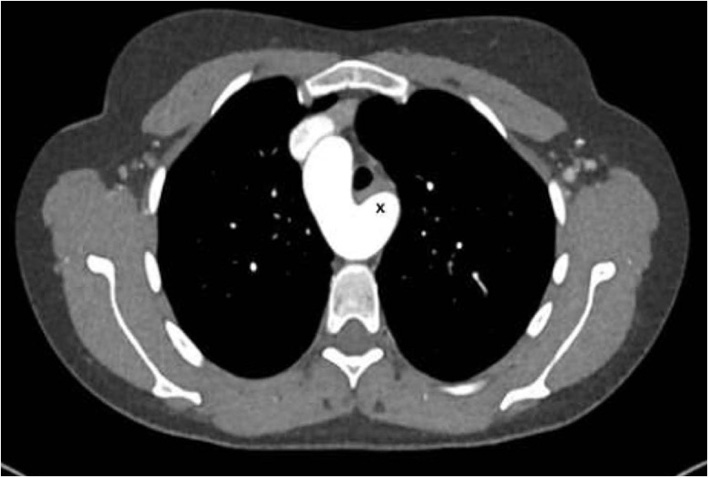

The lesion looked like an aorto-pulmonary window (as seen in the ascending aortic location) but in fact corresponded most probably to an extremely large ductus arteriosus confluence into the aorta (Figure 7). Indication for surgery was discussed since pulmonary artery pressure was not found to be irreversibly elevated.

Figure 7

Left: CT-angiography with a large patent ductus with a 2.5 cm confluence into the proximal descending aorta, functionally looking like an aorto-pulmonary window. Right: View in the 3-D reconstruction with the blue arrow demonstrating the site of the communication.

Surgery was performed through a median sternotomy. Prior to aortic canulation, both pulmonary artery branches were encircled with a tape. Thereafter, canulation of the ascending aorta and both vena cava was performed. Just after starting cardiopulmonary bypass, both pulmonary branches were clamped to avoid overfloating of the lungs through the very large aorto-pulmonary connection. At moderate hypothermia (core temperature 30°C), the circulation was briefly (15 min) interrupted, the aortic arch was clamped between the left common carotid and the left subclavian artery, and then antegrade cerebral perfusion was started with a flow of 600 ml at a temperature of 24°C. The ductus was opened longitudinally from its origin at the level of the pulmonary bifurcation until the confluence with the aorta. The large communication was closed using a vascular patch of Dacron with a running suture (Figure 8). We preferred to proceed during cardiac arrest to avoid two clamps close to each other in the operating field during closure of the aortic arch. Thereafter, the ductus was closed at its pulmonary origin, also using a patch. During rewarming, closure of the ventricular septal defect was performed with separate teflon-felt armed U-stitches. Weaning from cardiopulmonary bypass was uneventful and pulmonary pressure decreased to around 40% of the systemic pressure. Further postoperative evolution was uneventful.

Figure 8

Left: Intraoperative view through the pulmonary artery during circulatory arrest, showing the large communication with the descending aorta (blue arrow). Right: Closure with a vascular patch (blue arrow).